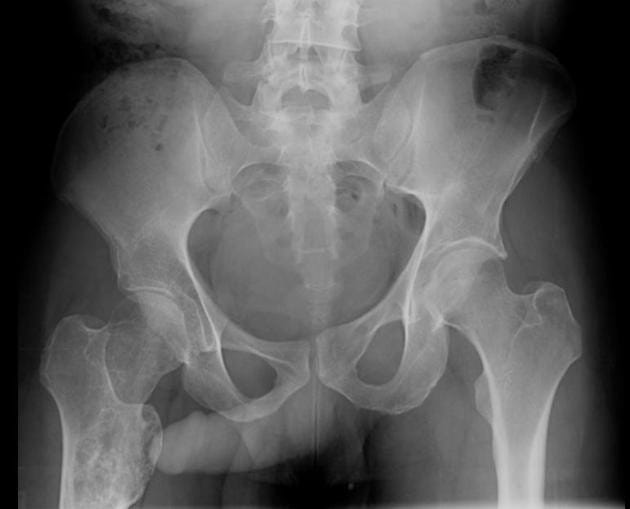

The John Thomas sign refers to the position of the penis on a pelvic X-ray in relation to a unilateral pelvic or hip pathology, such as a hip fracture. It is considered “positive” when the penis points toward the side of the pathology and “negative” when it points away. This phenomenon is thought to result from a patient’s unconscious attempt to lie on the injured side to reduce pain and immobilize the fracture, causing the penis to incline downward toward the affected side. Clinically, however, the sign has no reliable diagnostic value and is no better than chance at localizing pelvic or hip injuries.

The sign arises due to patient positioning and unconscious protective behavior—patients tend to lie on the injured side to mitigate pain and stabilize the injury, which causes the penis to point downward on the side of injury. This positional effect is projected radiographically as the shadow of the penis pointing toward the abnormality on the pelvic X-ray.